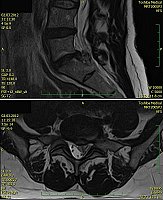

2. Muž, 41 let. Na MR objemná hernie L4/5 velikosti 11mm téměř vyplňující páteřní kanál, útlak nervových kořenů. Opakovaně doporučována operace, kterou pacient odmítl. Jako alternativu zvolil ozonoterapii s aplikací ozonu do disku L4/5 a periradikulárně. Byly aplikovány celkem 3 dávky ozonu. Viz obr.7a

Na kontrolním MR po 6 měsících je patrná výrazná redukce velikosti hernie, vymizely fragmenty, uvolnil se páteřní kanál a do značné míry i nervové kořeny. Subjektivně výrazná úleva téměř k normálu. Viz obr. 7b